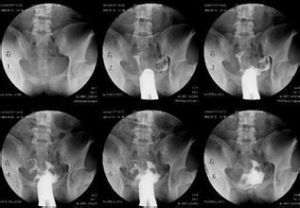

3.手術後輸卵管脫垂

輸卵管脫垂是經陰道子宮切除術後的併發症,在經腹部子宮切除術後則少見。觸動脫垂的輸卵管可引起劇烈的疼痛,可放射至病人腰部,病檢有助於確診。